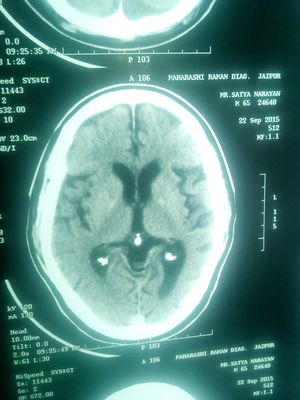

MRI Brain

What do this MRI shows??

Sarcoidosis